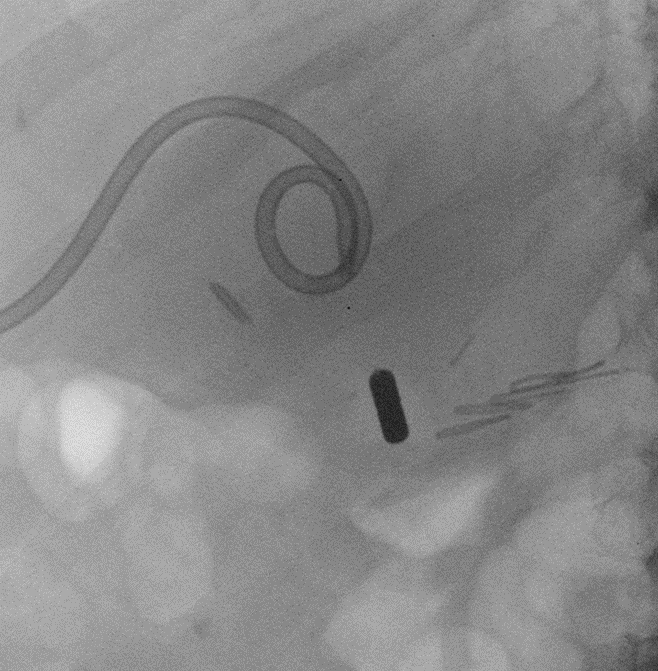

Immagine radiologica dei magneti a contatto

Nel trapianto di fegato la via biliare del donatore viene suturata a quella del ricevente (anastomosi): il restringimento di questa zona suturata è la complicanza più frequente (oltre il 10%) e avviene per un eccesso di cicatrizzazione. Dopo l’insuccesso nel superamento della ‘stenosi dell’anastomosi biliare’ con metodi endoscopici e radiologici “convenzionali”, l’equipe multidisciplinare guidata dal professor Guido Costamagna, Ordinario di Chirurgia Generale all’Università Cattolica e direttore dell’Unità Operativa di Endoscopia Digestiva Chirurgica del Gemelli, ha posizionato nelle vie biliari, a monte e a valle della stenosi, due piccoli magneti: quello inferiore tramite endoscopia e quello superiore attraverso il fegato, dopo puntura delle vie biliari dalla cute, in contemporanea. I due magneti, attraendosi, hanno determinato, in un paio di settimane, la riapertura (ricanalizzazione) del tratto biliare completamente occluso per compressione del tessuto cicatriziale, permettendo la successiva inserzione di protesi di plastica multiple per mantenere aperto il canale.

Il passaggio della bile, chiuso da una cicatrice invalicabile, è stato riaperto dalla forza di due piccoli magneti, che attraendosi l’un l’altro hanno ristabilito la continuità del dotto. L’intervento urgente e mini-invasivo di ricanalizzazione di una stenosi (restringimento) ‘invalicabile’ è lo straordinario traguardo clinico raggiunto nonostante l’emergenza Covid-19.